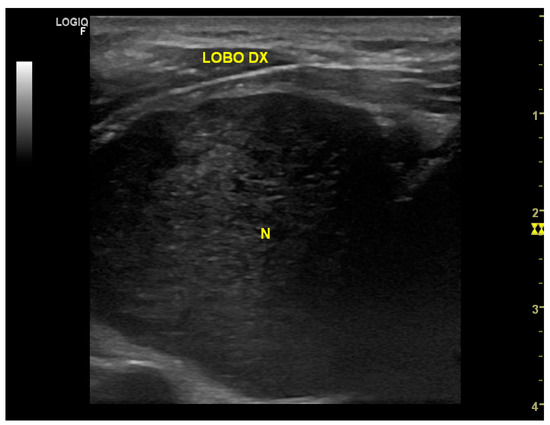

Background: Schwannomas, also called neurinomas, are rare benign tumors of the neural cells that can develop from the sheaths of nervous structures of several districts, although the most frequent sites are the cranial nerves (25%–45%). Rarely, cases show neck schwannomas in the thyroid parenchyma, while the cases of thyroid-bed schwannomas mimicking a thyroid-gland lesions are anecdotal. Methods: We report the case of a 70-year-old man with a preoperative-imaging diagnosis of a thyroid neoplasm, confirmed as Thyr 4 by fine-needle cytology. Results: During surgery, an extra-thyroidal lesion was discovered, determined to be a neck schwannoma through definitive pathology. A literature review of cases of thyroid-bed-lesion schwannomas misinterpreted as thyroid neoplasms was carried out. Conclusions: In the case of suspicious extra-thyroidal lesions, we advocate for a close routine cooperation between the cytologist, the radiologist, and the surgeon in the attempt to reach an accurate preoperative diagnosis. Full article

Figure 1